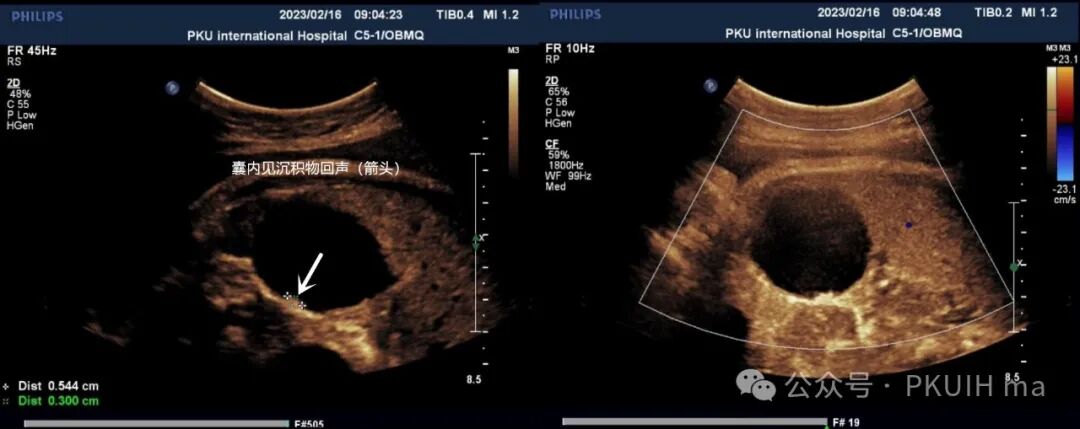

在随后的随访观察中(如下图)发现囊肿大小和内部回声有变化。最终考虑是卵巢出血性囊肿(卵巢扭转待除外)